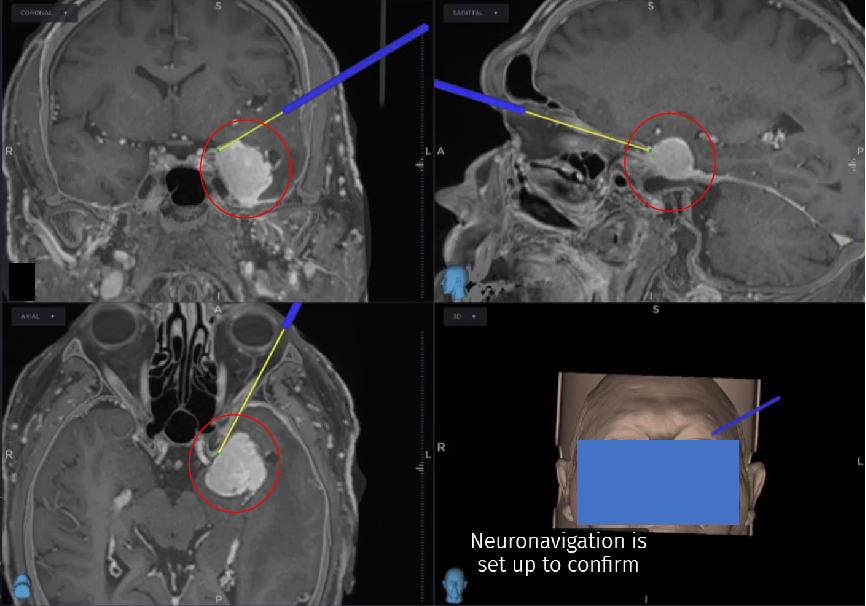

神经导航定位